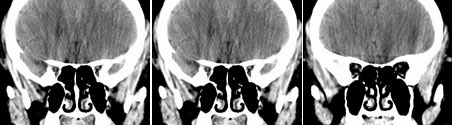

性别  女    年龄 45

阵发性头痛伴视物不清两年余

鞍区垂体窝内见一巨大类椭圆性软组织块影,前后床突受压移位、变薄,鞍底凹陷,应当能明确诊断垂体瘤。不过最好能做个mri看看视神经受累情况

蝶鞍内圆形密度不均匀,包膜完整肿块影,前床突与鞍底变薄.

意见:垂体大腺瘤.

本病例单凭ct检查是很难定位准确的,是鞍上病变侵犯鞍内、还是鞍内病变向鞍上生长?

1、如果鞍内肿瘤突破鞍隔,向鞍上生长,考虑垂体腺瘤,其典型表现是肿瘤呈"8"字征。

2、如果是鞍上肿瘤侵犯鞍内,要考虑鞍区脑膜瘤、生殖细胞瘤、实性颅咽管瘤(多为囊性、少数也可实性)、转移瘤、垂体柄胶质细胞瘤。